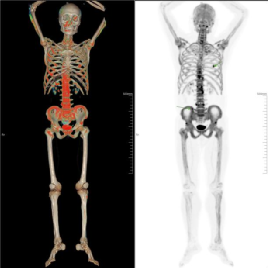

第二位患者为48岁X先生,有肺癌病史 2 余年,此次为定期复查,需精准排查是否存在骨转移情况。通过这次18F-NaF PET/CT 骨扫描,不仅为患者的骨骼健康状况提供了精准评估依据,更标志着科室在骨骼系统疾病精准诊断领域迈出关键一步,为区域内患者带来了更先进、高效的诊疗选择。